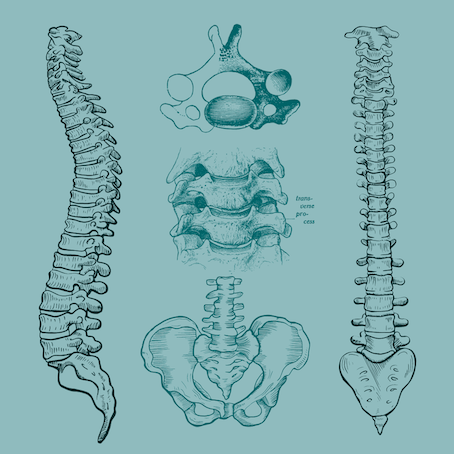

1. Mapeo de la columna.

- Identificando las estructuras de la columna y su función.

- Esqueleto axial y apendicular, yo soy-yo hago

- Identificando las estructuras de la columna y su movimiento en el espacio.

4. La columna como guardiana del sistema nervioso.

- La columna blanda, patrón prespinal y espinal.